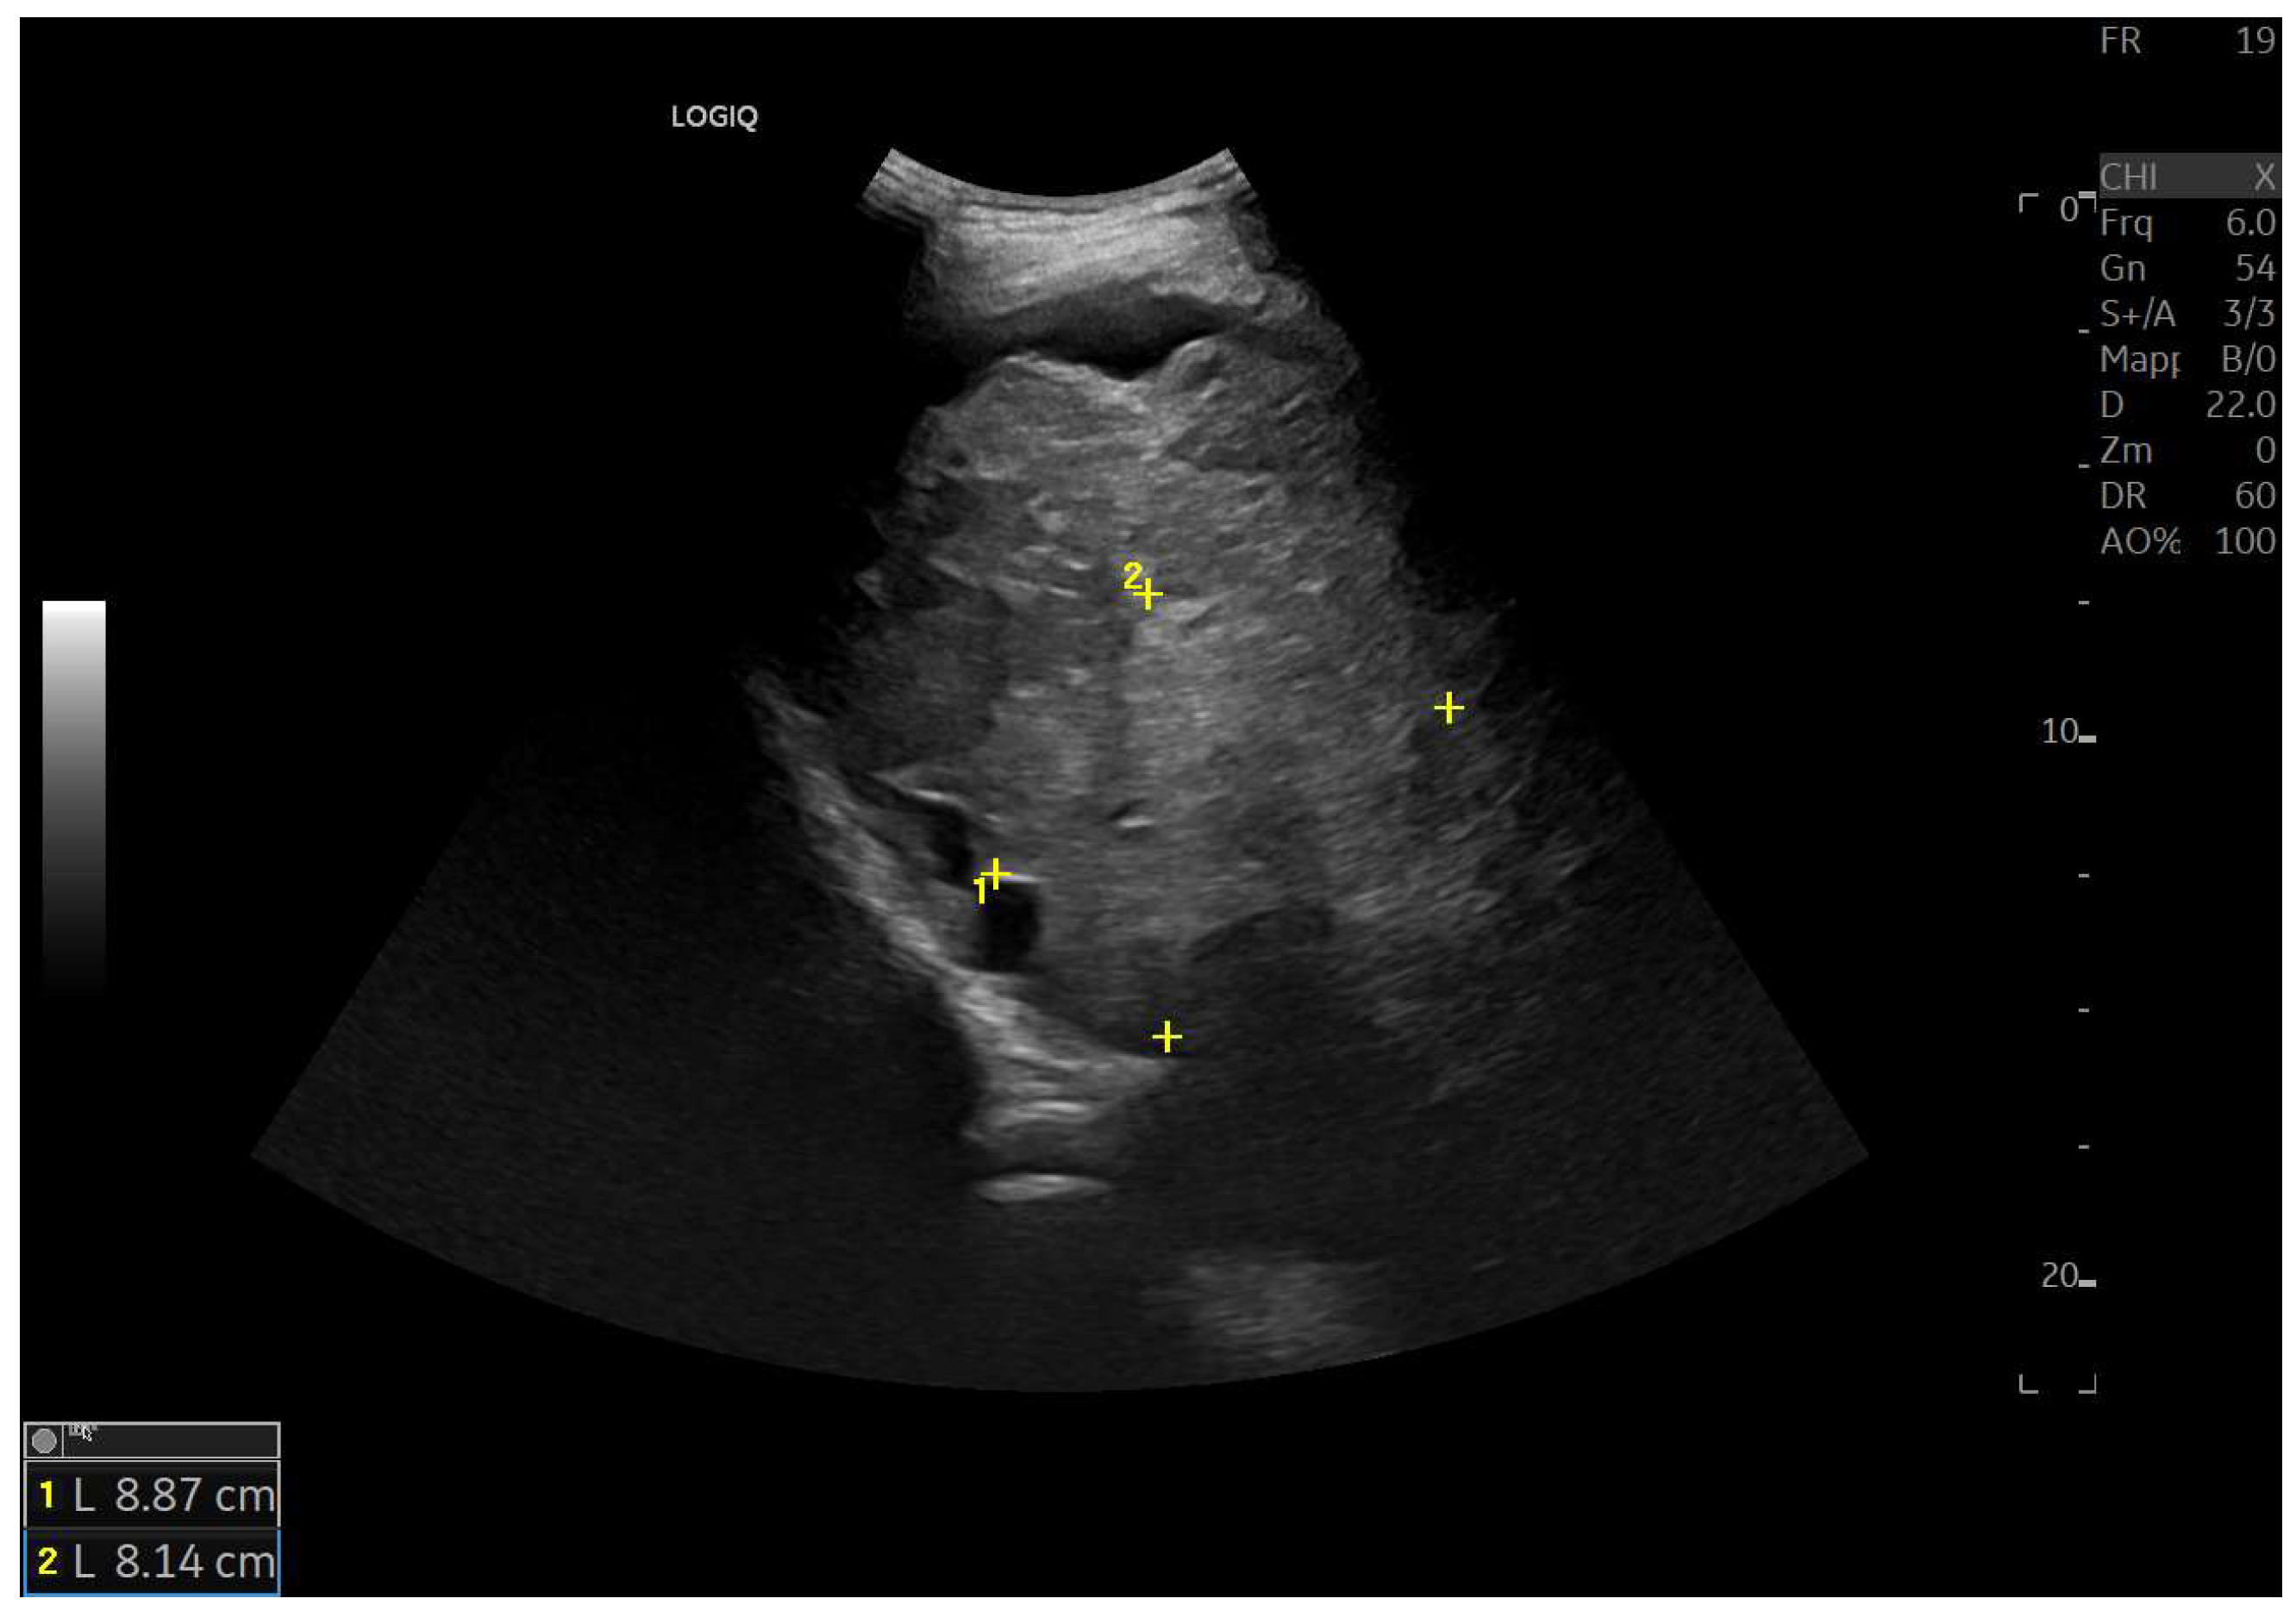

Figure 6.

Diffuse echostructural change of the left lobe with a heterogeneous hyperechoic area measuring 89 × 81 mm.

Figure 7.

Hypotrophy of the right lobe. Nodular profiles. Markedly heterogeneous echostructure, with increased fibrous component and fibrous trabeculae delimiting pseudo-nodular areas, within the context of a vascular-type cirrhosis.

Figure 8.

Marked hypertrophy of the left lobe, which partially occupies the left hypochondrium.